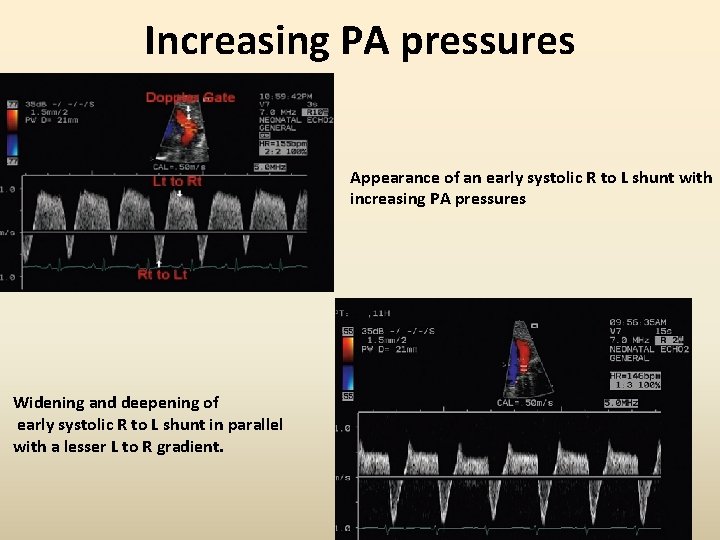

Increasing PA pressures Appearance of an early systolic R to L shunt with increasing PA pressures Widening and deepening of early systolic R to L shunt in parallel with a lesser L to R gradient.